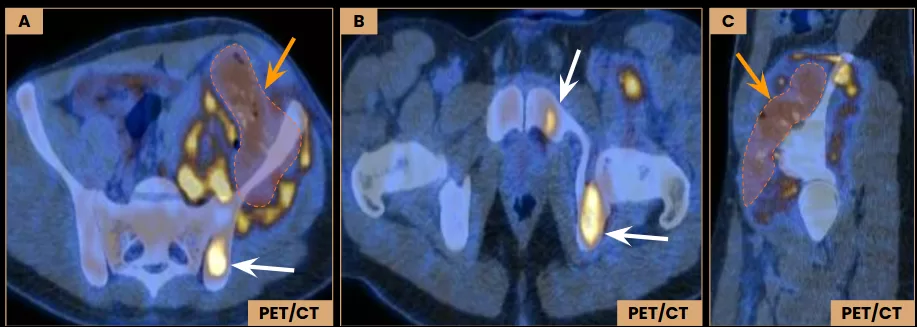

Diagnostic Imaging – PET/CT

Images A – C: Axial and sagittal PET/CT images demonstrate FDG avidity of the lesion, with a maximum SUV of 12.4. Central areas of reduced uptake suggest necrosis (arrows – orange). Additional hypermetabolic foci are seen in the left iliac body, posterior aspect of the ischium, and ipsilateral pubic ramus (arrows – white). All of them without corresponding structural abnormalities on CT images.

Diagnostic Imaging – PET/CT and MRI

Images B and D: Axial MRI images show subtle enhancement in the left posterior iliac body (arrow – red), along with signal heterogeneity in the posterior aspect of the ischium (arrow – green) and in the pubic ramus (arrow). These findings correspond to hypermetabolic regions (dashed ellipses) identified on axial PET/CT images (A and C).

Post-chemotherapy findings after five treatment cycles.

Images A and B: Axial PET/CT images show a slight reduction in the soft tissue component of the lesion (dashed lines), with decreased FDG uptake (SUVmax 6.9, previous 12.4). The lesion in the left iliac is no longer FDG-avid (arrows).